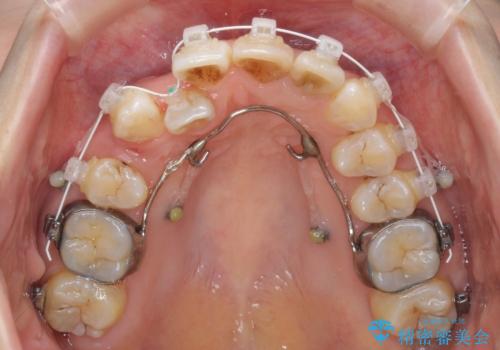

- 重なった前歯を邪魔に感じ、汚れも溜まりやすいことを気にして来院された患者様です。

右上前から2番目の歯が内側に転位しているため、上顎の正中は右にずれていました。

右上4番目の歯を抜歯し、上顎裏側に補助装置を装着して左の歯列全体を後方に移動させながら、正中を合わせるようにして行くこととしました。

内側に転位していた歯はきれいに歯列に収まり、清掃性が著しく改善しました。

元々神経の失活してしまっている前歯2本は変色が目立つようになってきたため、今後セラミッククラウンによる補綴治療を行う予定です。